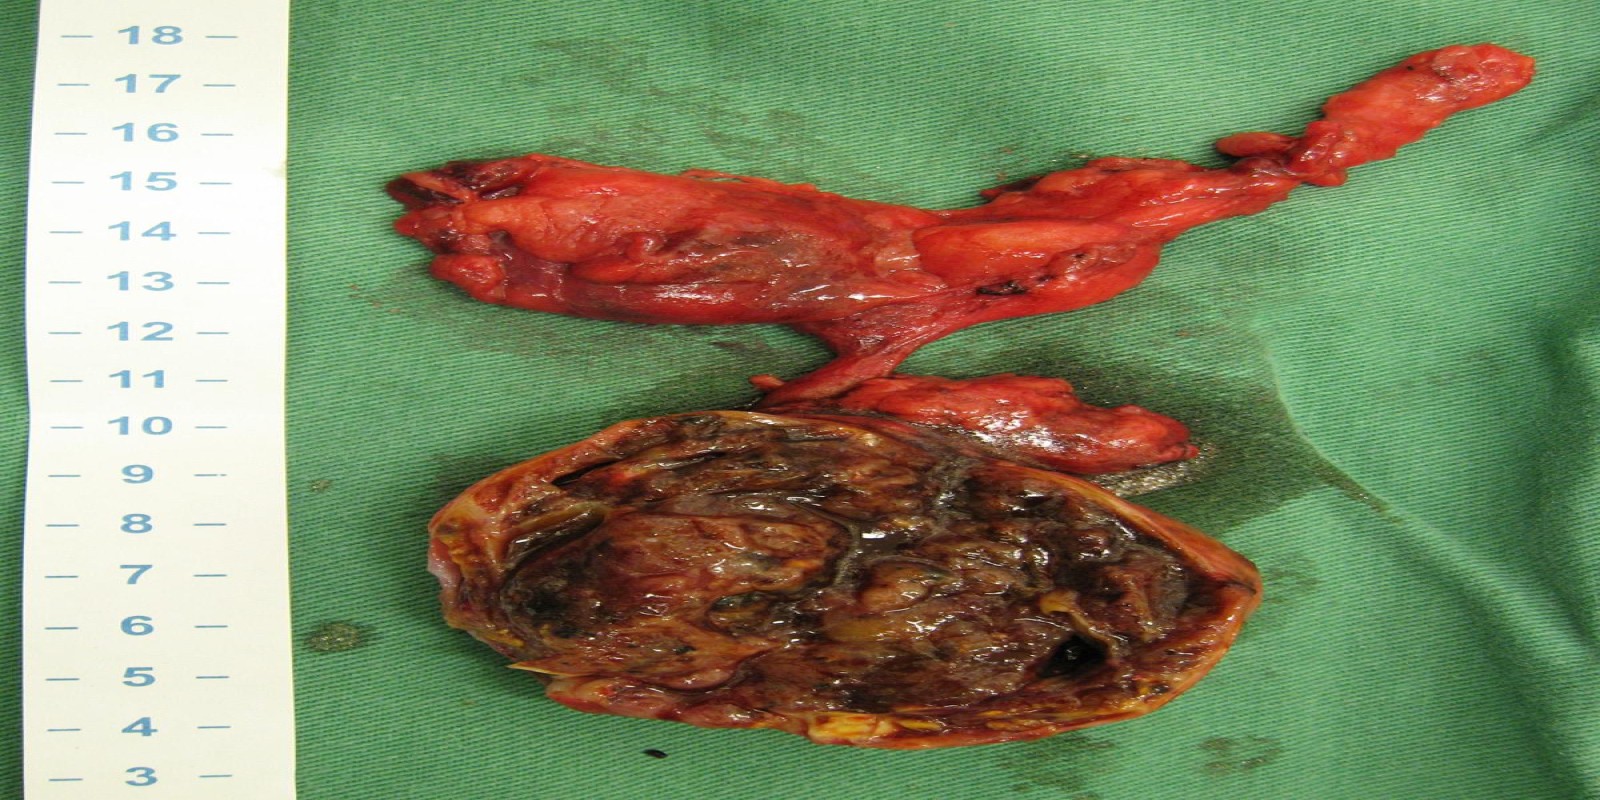

Tireóide ectópica mediastinal

Ectopic Mediastinal Thyroid